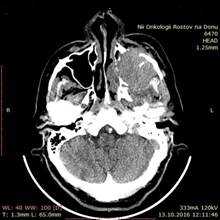

Больной В., 1947 года рождения, поступил в отделение опухолей головы и шеи ФГБУ «РНИОИ» МЗ РФ 17.10.2016 г. с жалобами на опухоль в области левой щеки. При осмотре – лимфатические узлы шеи не увеличены, носовое дыхание не затруднено, лицо асимметрично за счет распространяющейся в мягкие ткани левой щеки опухоли левой верхнечелюстной пазухи. При пальпации деструкция нижнеорбитального края не определяется. При передней риноскопии опухоль не определяется. Остальные ЛОР-органы без видимой онкопатологии. СРКТ от 13.10.2016 г.: «Слева опухоль верхнечелюстной пазухи 5,6х5 см с неоднородной структурой, прорастанием ее передней стенки с распространением мягкотканого компонента опухоли на мягкие ткани лица, участок деструкции альвеолярного края верхней челюсти слева» (рис. 2).

Рис. 2. СРКТ придаточных пазух носа: слева опухоль верхнечелюстной пазухи 5,6х5 см с неоднородной структурой, прорастанием ее передней стенки с распространением мягкотканого компонента опухоли на мягкие ткани лица, участок деструкции альвеолярного края верхней челюсти слева